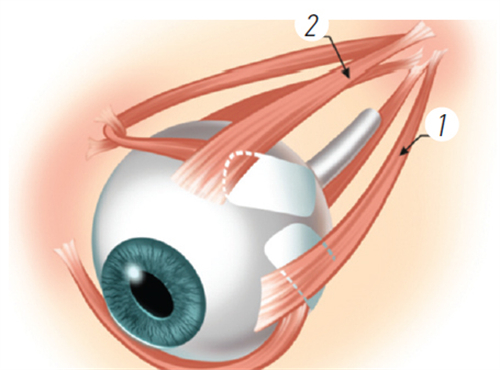

在可靠技术方面,雷医生擅长玻璃体视网膜手术,对复杂性视网膜脱离、糖尿病视网膜病变、黄斑裂孔、黄斑前膜等疾病有独到的治疗经验。

她采用小创口玻璃体切割技术,结合较可靠的眼科检查设备,为患者制定个性化治疗方案。

小创口玻璃体切割术:使用25G/27G超小创口系统,创伤小、修复快

复杂性视网膜脱离复位术:成功概率高,术后视力修复良好

黄斑手术:包括黄斑前膜剥除、黄斑裂孔修复等